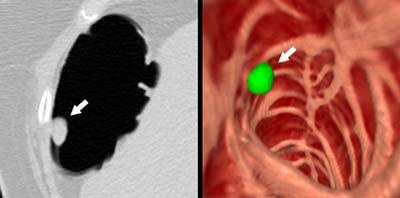

![]() |

| Above, 8-mm polyp in the sigmoid colon detected by CAD. Left: axial image showing the polyp (arrow). Right: Endoscopic view of the polyp. Green indicates a region identified by CAD as a polyp. Image courtesy of Dr. Hiro Yoshida. |

| Ten-millimeter polyp in the hepatic flexure detected by CAD. Left: axial image showing the polyp (arrow). Right: Endoscopic view of the polyp. Green indicates a region identified by CAD as a polyp. Image courtesy of Dr. Hiro Yoshida. |